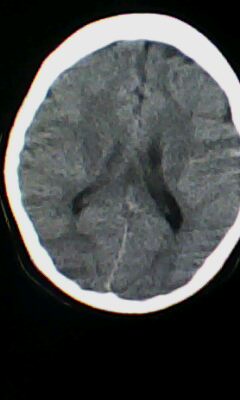

标题: CT25338:女 14岁 3岁时检查为脑积水 现在发育滞后 偶有尿失 [打印本页]

标题: CT25338:女 14岁 3岁时检查为脑积水 现在发育滞后 偶有尿失

颅脑ct轴位平扫颅内未见明确异常。

颅脑ct轴位平扫颅内未见明确异常,建议mri。

左侧颞枕叶区密度异常?